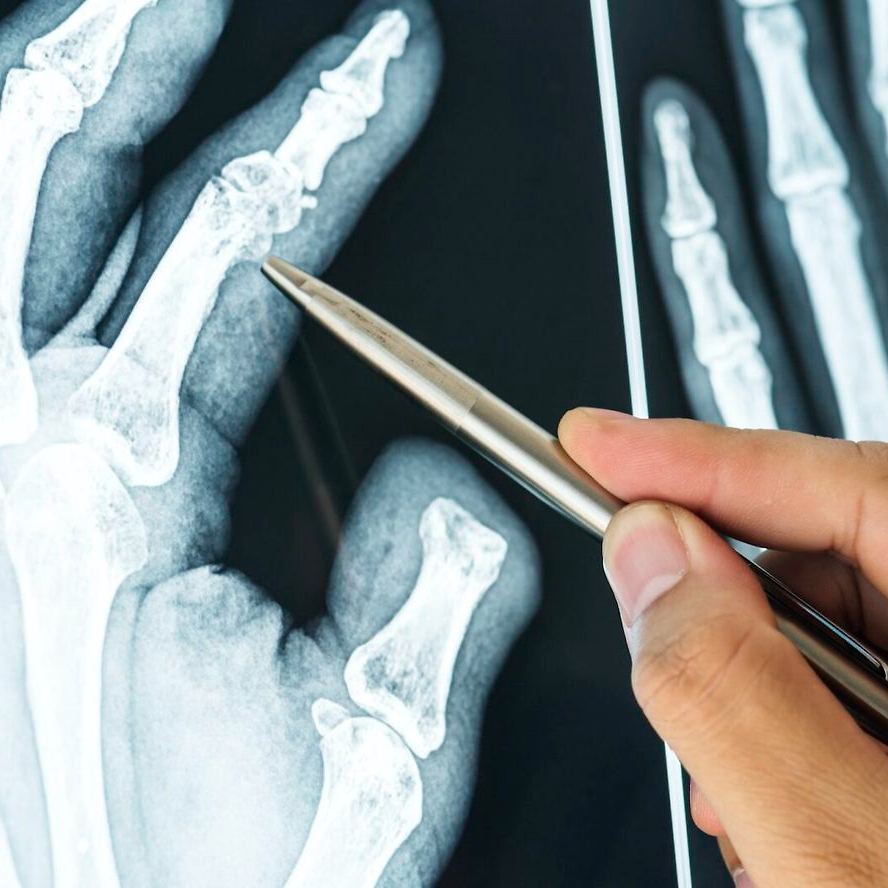

발가락 골절 증상·진단 포인트

- 국소 붓기·홍반·멍

- 걸을 때 날카로운 통증 또는 불안정감

- X-ray 2 방향 촬영이 1차 진단 표준

- 모호할 경우 CT/MRI 추가